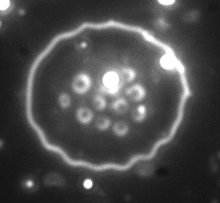

A Bartonella bacilliformis (tj. lekko wydłużony, pręcikowaty gatunek bakterii Bartonella) wytwarza zewnątrzkomórkowe białko zwane „deforminą”, które może niezależnie tworzyć wgłębienia i rowki w błonach czerwonych krwinek.

Rysunek 1. Inwaginacje erytrocytów spowodowane przez czynnik deformujący (deformin) B. bacilliformis.

Rysunek 2. Bartonella bacilliformis wnika do erytrocytów i deformuje powierzchnię ich błon.

Rysunek 3. Inwaginacja erytrocytów prawdopodobnie spowodowana przez Bartonella spp. u małpy.